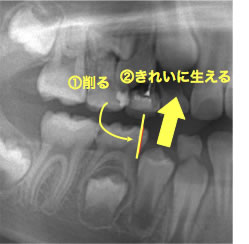

そこで、抜けた歯の後ろにある乳歯の一部を削ることで永久歯の生えてくるスペースを確保する方法があります。削るのは主にエナメル質と呼ばれる歯の表層部分で、この部分を削る分にはほとんど痛みは感じません。また、歯の生え変わりの時期のお子さんの乳歯の下には、永久歯がすぐ近くまで控えており乳歯の根を吸収して短くしています。これにより歯を削っても痛みを感じにくい傾向があります。

6歳臼歯(第一大臼歯)が手前の乳歯にひっかかっている状態。

奥歯が手前の乳臼歯にひっかかり、きちんと生えてこれない状態です。専門的には、第一大臼歯の「異所萌出」と言います。

上の6歳臼歯に多く、右左どちらかにだけ認められることが多いです。

① 乳臼歯が大きい

② 乳臼歯の後ろ、あるいは6歳臼歯の手前の形が膨らんでいる

③ 上顎歯列の幅が狭い

そのままにすると、6歳臼歯がさらに前に傾いて噛み合わせが悪くなります。また、虫歯になってしまう事があります。

引っかかる原因の乳臼歯を抜くと、6歳臼歯は前に寄りながら萌出してしまうので、抜いた乳臼歯の下にある永久歯が萌出するスペースが無くなってしまいます。

ブラケットを装着して、6歳臼歯を後ろに移動させ、萌出させる事です。状態によっては、他の方法もあります。

手間の乳臼歯は、根が溶けて吸収しているので、早く抜けてしまう事が多いです。そのような場合、せっかく良い位置に移動させた6歳臼歯が、再び手間に倒れてきてしまうので、保隙装置を装着する必要があります。

6歳臼歯の放出遅延をそのままにするとさらに前に傾いて

噛み合わせが悪くなります。

また、虫歯になってしまう事があります。

引っかかる原因の乳臼歯を抜くと、6歳臼歯は前に寄りながら萌出してしまうので、

抜いた乳臼歯の下にある永久歯が萌出するスペースが無くなってしまいます。